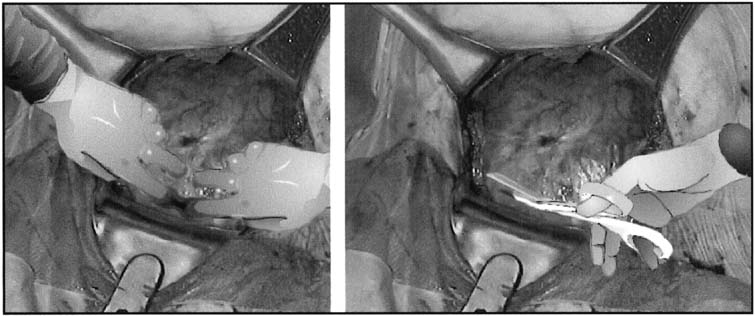

Delivery of the Fetus

After the uterine incision has been made, the fetal membranes, if still intact, are ruptured with an Allis clamp. If the fetus is in a noncephalic presentation, leaving the membranes intact until the fetal feet or head can be moved into the uterine incision will increase the ease of delivery. When the fetus is in a cephalic presentation, delivery is performed by the surgeons placing their dominant hand into the uterine cavity and elevating the fetal head into the uterine incision (Fig. 6). If the fetus is not in an occiput anterior position, rotating the head into this position will allow the fetal neck to extend around the upper portion of the incised myometrium and more closely mimic the cardinal movements of vaginal delivery. When the fetal head is impacted in the maternal pelvis, such as in deep transverse arrest, there are a number of options to assist with delivery of the fetal head. The surgeon can place a hand in the lower uterine segment in the standard fashion to cup and then disengage the fetal head. Care must be taken by the surgeon not to flex the wrist, because this often causes extension of the uterine incision caudally toward the bladder and vagina. If this does not work, an assistant can place a sterile, gloved hand into the vagina from the introitus and disengage the fetal head from below (Fig. 7). Another option is for the surgeon to the dominant hand between the lower uterine segment and the reflected bladder and attempt to disengage the head by cupping it through the lower uterine segment. It is our experience that care must be taken with this maneuver to ensure that the bladder is not damaged by inadvertent blunt cystotomy.

Fig. 6. Extraction of the fetal head. The surgeon's dominant hand is placed into the uterine incision so that the back of the hand is against the inside of the lower uterine segment and the fingers cup the fetal head. Firm, gentle traction is used to elevate the fetal head toward the incision. The fetal head may then be rotated to an occiput anterior position and delivered through the uterine incision with the assistance of fundal pressure.

Fig. 7. Disimpaction of the fetal head. When the fetal head has descended so far into the vagina that extraction of the fetal head is difficult, having an assistant place a gloved hand into the vagina and elevate the fetal head from below can increase the ease of delivery and decrease the trauma to the lower uterine segment and vagina.